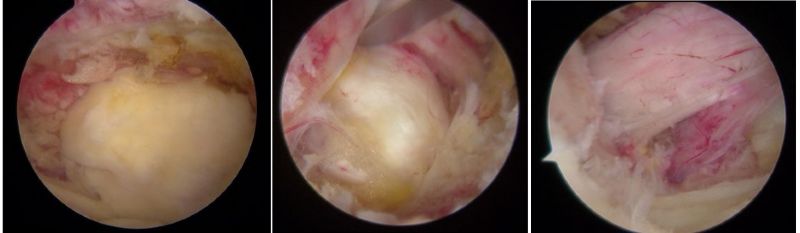

骨科內鏡下的腰椎組織